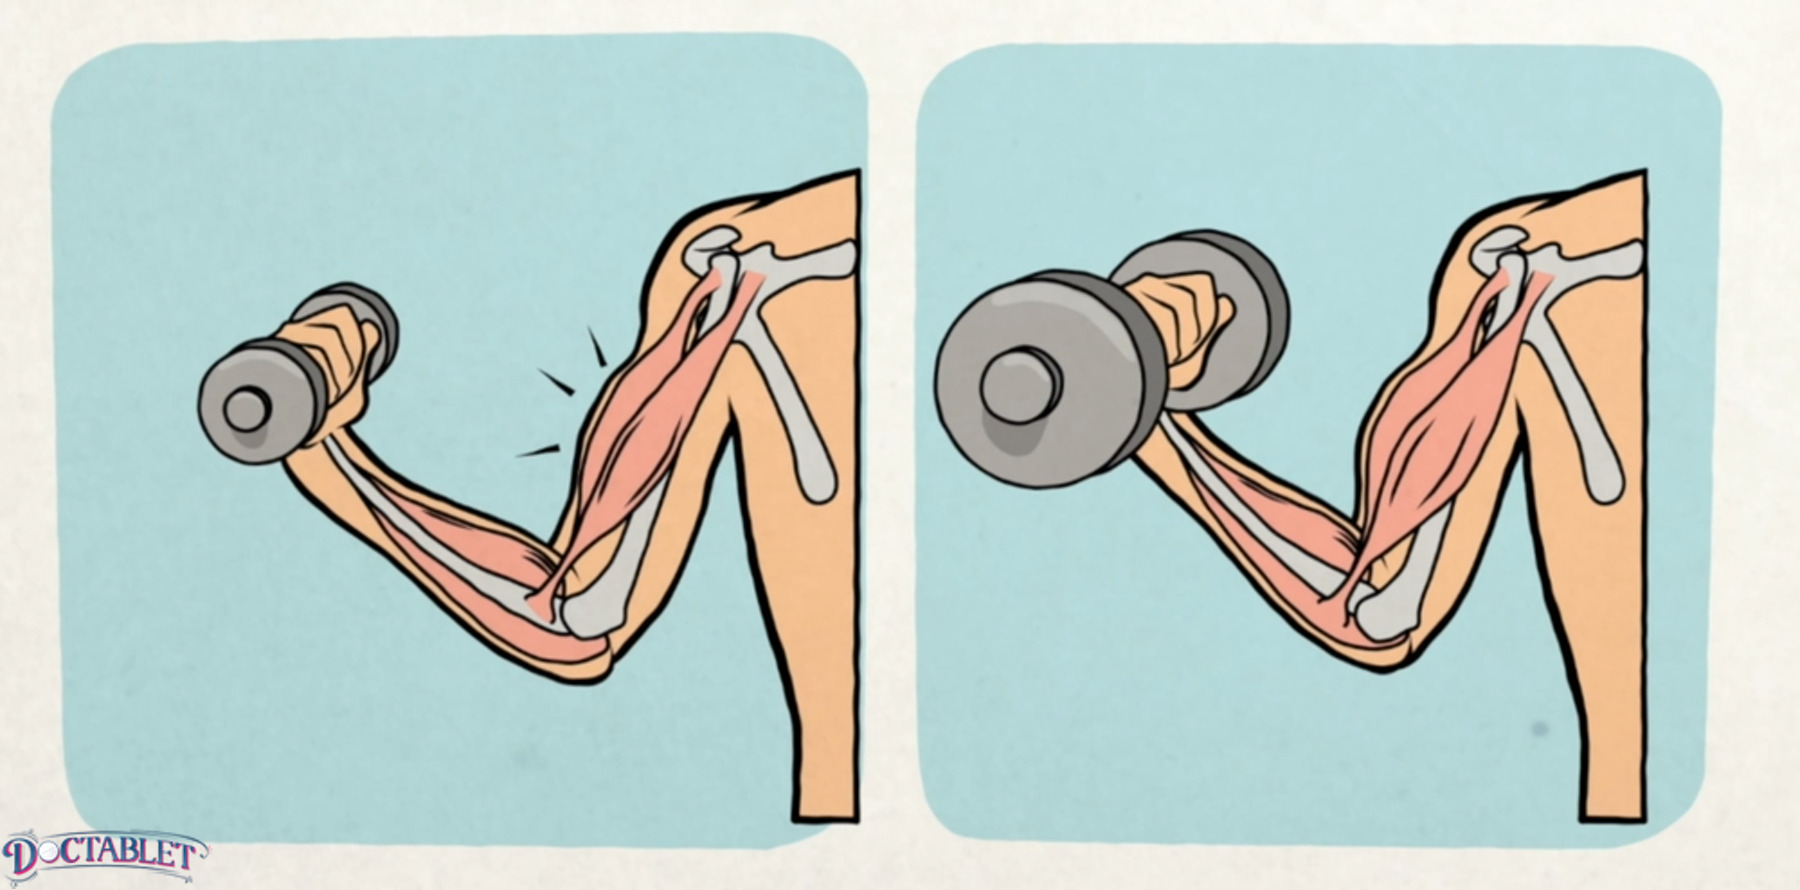

Ejercicios con bajo peso y alta repetición que desarrollan tono, resistencia y fuerza. Este es el tipo de ejercicio que hacen los ciclistas y corredores.

Ejercicios con alto peso y poca repetición. Esto desarrolla músculos grandes y aumenta la fuerza del músculo.